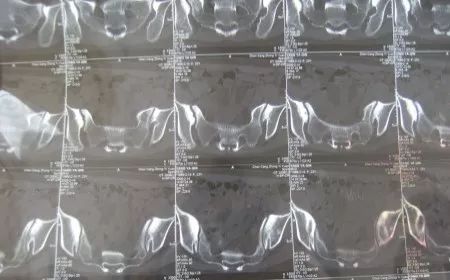

根据国内外研究和长期临床数据,相对于成年人,HLA-B27检测对于幼年强直性脊柱炎更为重要。临床怀疑本病的儿童要做HLA-B27检测,适时做骶髂关节CT或MRI检查,以利早期诊断,早期治疗,改善预后。